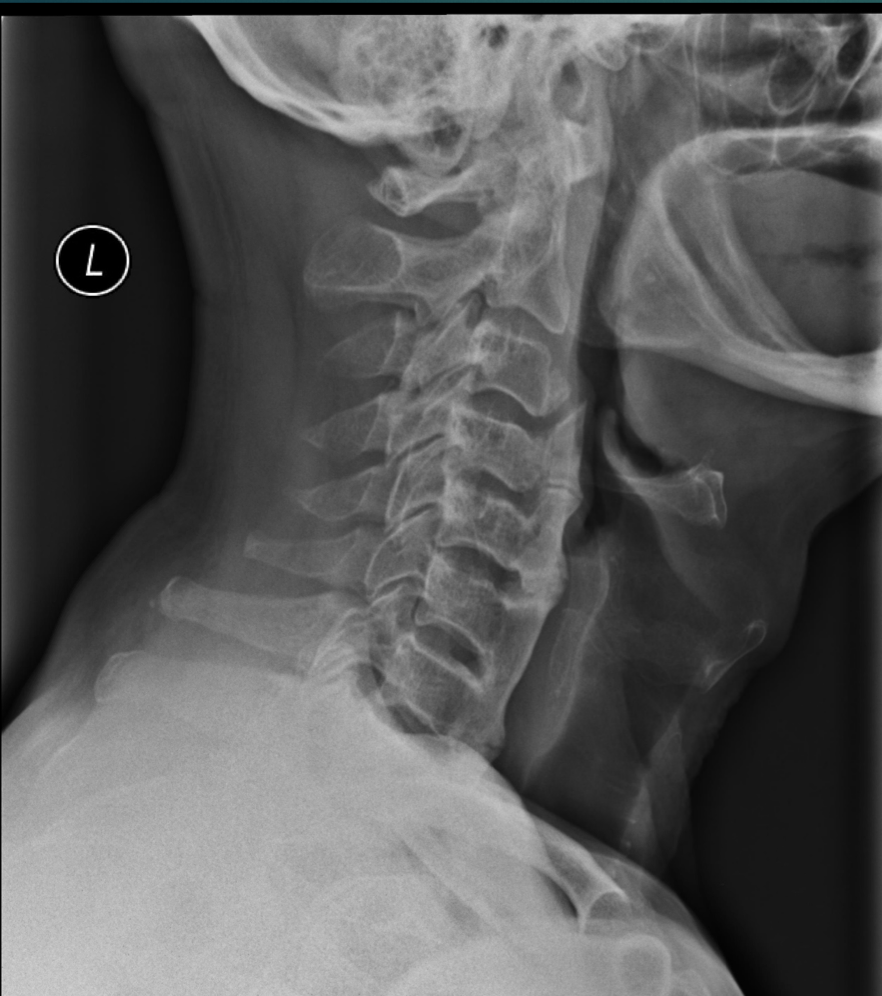

52 YO M. Complains of difficulty with eating.

• Hyperostosis of ALL

• NORMAL disc height

• T or L shape (orange)

• Look for OPLL 85% of the time - look for this because of central canal stenosis

Think: DISH